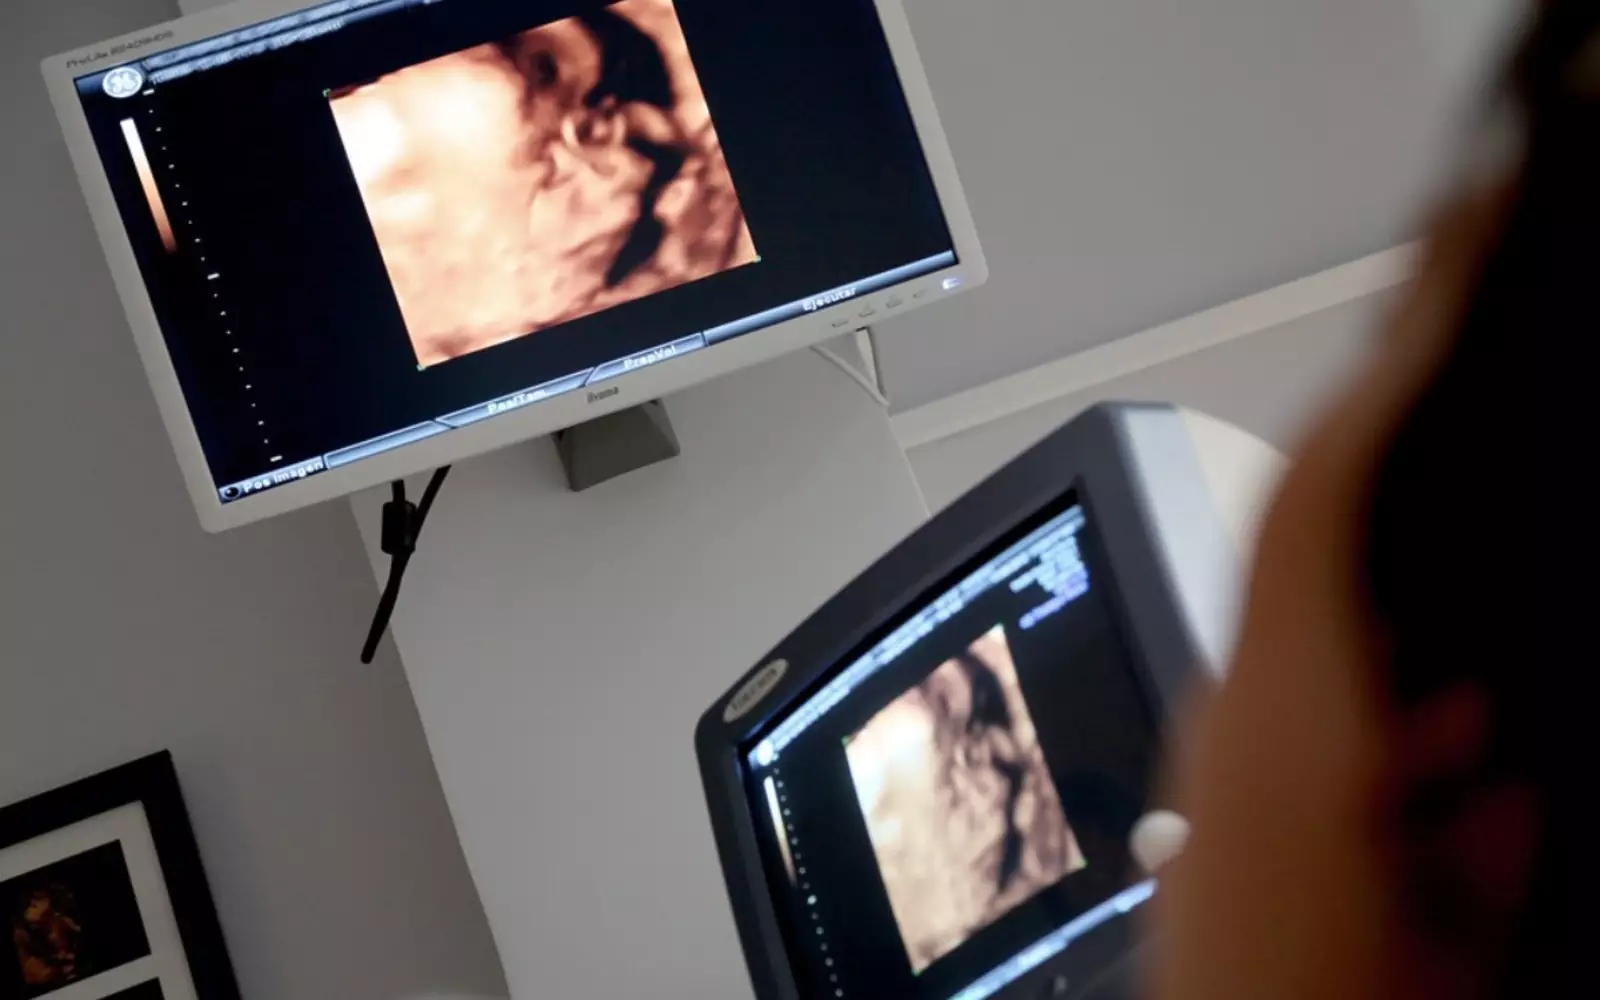

Согласно новому исследованию ученых из университета имени Бен-Гуриона (Израиль) обычное пренатальное УЗИ, сделанное во втором триместре беременности, может выявить ранние признаки расстройства аутистического спектра (РАС) у ребенка.

Израильские специалисты изучили данные сотен пренатальных ультразвуковых исследований и обнаружили аномалии в сердце, почках и голове у 30% плодов, у которых позже развилось расстройство аутистического спектра. Эти аномалии были связаны с последующей тяжестью симптомов РАС и чаще выявлялись у девочек, чем у мальчиков.

«Результаты нашего исследования показали, что определенные типы РАС, которые включают аномалии других органов, начинаются и могут быть обнаружены еще в утробе матери. Врачи могут использовать обнаруженные нами аномалии, различимые во время обычного УЗИ, для оценки вероятности рождения ребенка с расстройством аутистического спектра», — говорит профессор Идан Менаше, руководитель исследовательской группы.